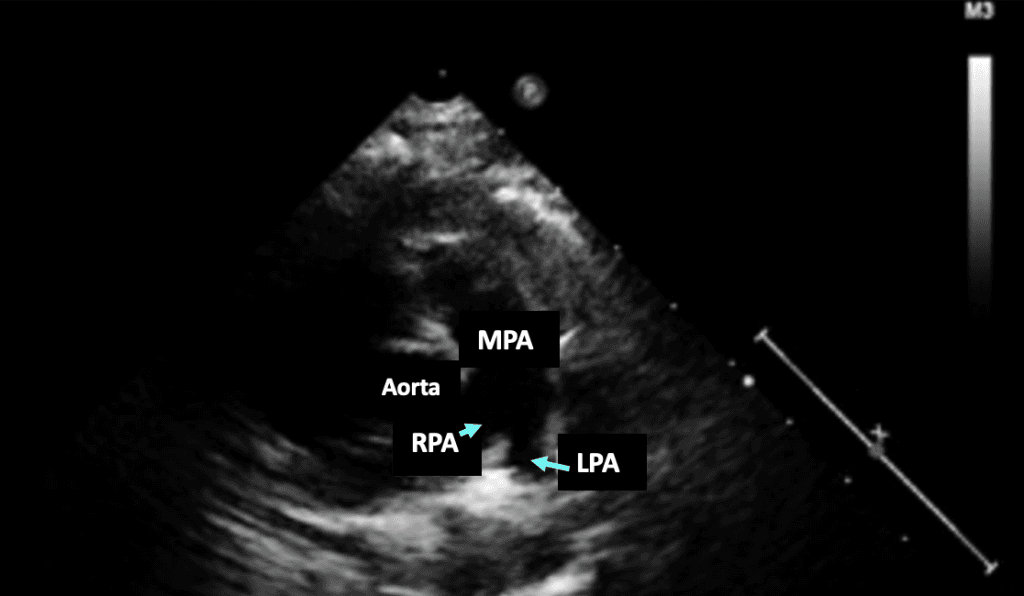

Learn to identify echocardiographic findings, understand pulmonary hypertension classifications, and use echo for treatment assessment. Enhance patient care and outcomes.

Accurately identify and interpret echocardiographic findings.

Recognize findings on echocardiographic exam images